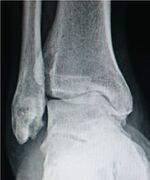

- For the ankle, the Kellgren–Lawrence scale, as described for the hip, has been recommended.[16] The distances between the bones in the ankle are normally as follows:[17]

- Talus - medial malleolus: 1.70 ± 0.13 mm

- Talus - tibial plafond: 2.04 ± 0.29 mm

- Talus - lateral malleolus: 2.13 ± 0.20 mm